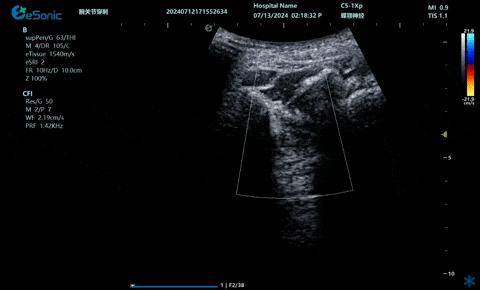

04

超声引导下神经根阻滞,也可以

做腰神经后支

9.3.gif